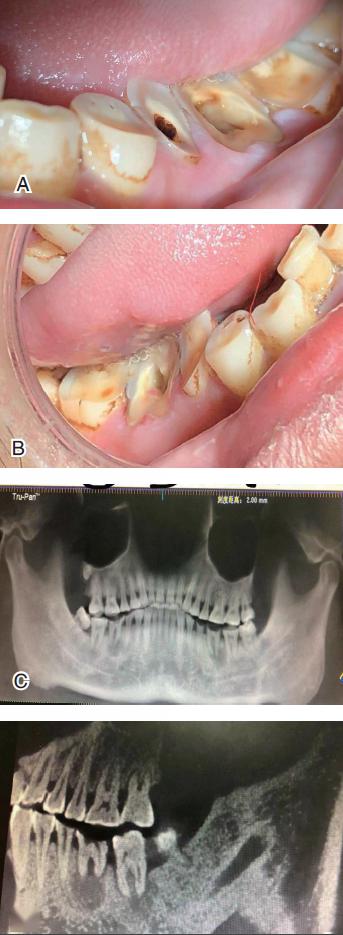

34 岁的槟榔咀嚼者的牙齿严重磨耗,根尖病变,下颌角及颞颌关节的

牙齿磨损

牙齿磨损的疾病介绍

牙体磨损